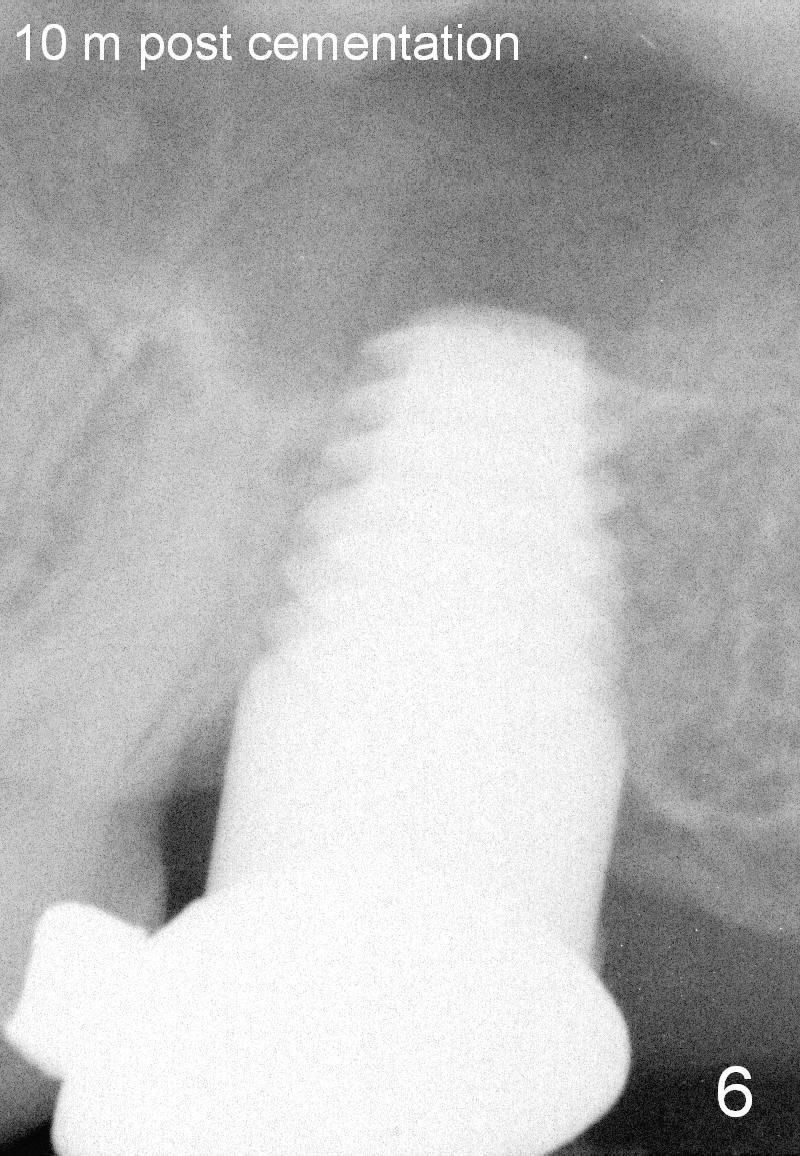

Four and a half months postop, bone resorption is slightly more severe (Fig.4) than immediately postop (Fig.3). Fig.5 is taken 1.5 weeks post cementation. Bone resorption appears to be halted 10 months (Fig.6) and 1.5 years (Fig.7) post cementation, respectively. The implant threads remain unexposed 4 years 4 months (Fig.8) and 5 years 4 months post cementation.